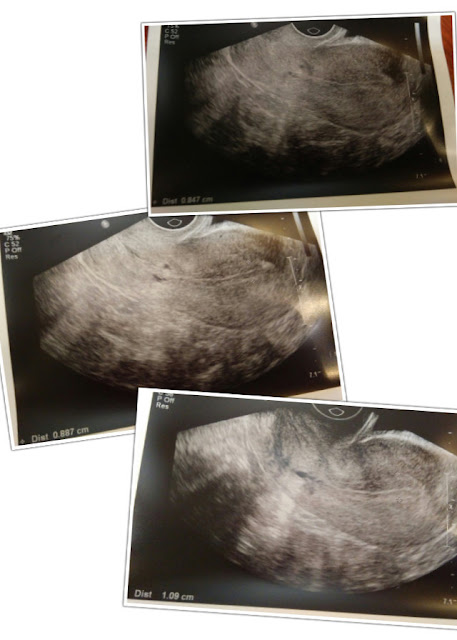

日記8月12日,星期三,月經後的第十三天。

今天先去做針灸,之後便到診所準備抽血及照內膜。

如果一切都沒有問題便可以前往泰國放胎。

這次和上個月相比真是放鬆了很多,完全沒有刻意去食什麼東西,

就只是照醫生的分咐去食藥,除了針灸之外便什麼都沒有了,

整體感覺輕鬆。

再加上上星期五已照這一次,知道那時內膜的厚度約0.6cm,

所以我是有信心今次的厚度應該是可以的。

只要我今次的厚度是介乎0.8-1.2cm次間,便沒有問題了。

醫生替我照了很多個角度,厚度介乎0.8至於1之間。

其中有一個最厚的厚度是1.3,我聽到自然內心一沉,

1.3不就是又過厚了嗎?

還好醫生解釋說這是邊位,不能佢準,

要看見全條子宮的彎條所度出的厚度才能作準,

還好沒事,差點把我嚇得半死了。

之後再抽抽血,等明天再取報告後便可確定能否成行。

看完醫生後馬上把照片傳給周小姐,她說應該可以了,

明天可以開始加藥,但最終能否去泰國也要等明天看完驗血報告後由醫生決定。